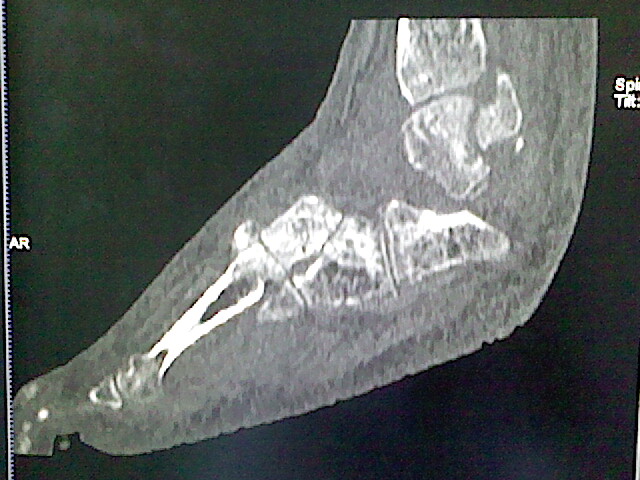

标题: CT16814:男,76岁,左小腿疼痛,不能站立 大家给看看 [打印本页]

男,76岁,左小腿疼痛,不能站立

本例骨质改变主要表现为滑膜或韧带区的骨侵蚀融解(胫腓联合区骨质破坏无硬化边),距骨后部骨质破坏区有硬化边及死骨样改变.所以,本例考虑关节结核可能性大,绒毛膜结节性滑膜炎多发于中年,且极少见于膝髋以外的关节,骨质硬坏也以压陷吸收为主,有明显的硬化边,骨膜增生呈结节状(可以mr鉴别),所以本例暂除外.

另不除外可引起相似表现的其他炎症如布氏杆菌性关节炎等